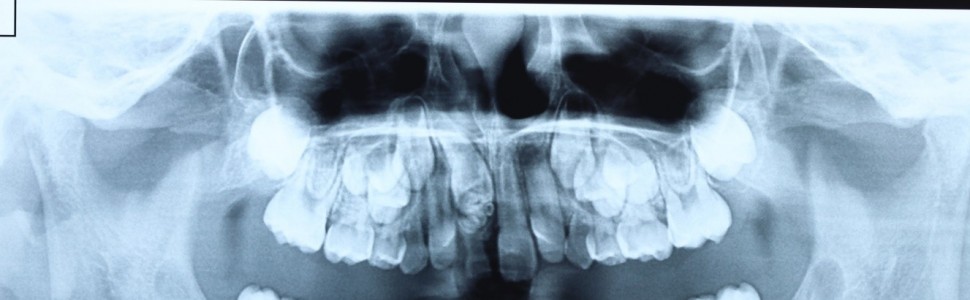

Zębiaki to jedne z najczęstszych guzów zębopochodnych występujących w jamie ustnej. Ich etiologia nie jest do końca poznana. Większość autorów dzieli je na zębiaki złożone i zestawne. Najczęstszym objawem sugerującym występowanie zębiaka jest zaburzone wyrzynanie zębów stałych. Wykrywane są zazwyczaj przypadkowo na zdjęciach rentgenowskich. W artykule został przedstawiony przypadek 7-letniego pacjenta, który zgłosił się z rodzicem do poradni w celu konsultacji i leczenia zmiany, wykrytej na zdjęciu rentgenowskim, nad przetrwałym zębem mlecznym 51. Po analizie badania podmiotowego, przedmiotowego oraz ocenie zdjęcia pantomograficznego zaplanowano zabieg wyłuszczenia guza, wykonanie badania histopatologicznego oraz usunięcie przetrwałego zęba mlecznego 51. Zatrzymany ząb 11 pozostawiono do obserwacji i samoistnej erupcji. W pracy autorzy zwracają uwagę na fakt występowania w praktyce klinicznej zębiaków i konieczność prawidłowej diagnostyki i leczenia tej anomalii. W celu prawidłowego rozpoznania i leczenia zębiaków konieczna jest współpraca doświadczonego specjalisty chirurgii stomatologicznej lub szczękowo-twarzowej oraz lekarza ortodonty.

Odontomas are among the most common odontogenic tumors found in the oral cavity. Their etiology is not fully understood. Majority of authors divide them into complex and compound odontomas The most frequent symptom suggesting the occurrence of an odontoma is the disturbance in permanent tooth eruption. They are typically detected accidentally on radiographic images. The paper presents the case of a 7-year-old patient who visited the clinic for consultation and treatment of a lesion detected on an X-ray over a persistent deciduous tooth 51. After the subjective and physical examination, pantomographic image analysis, the procedure of enucleation of the tumor and histopathological examination as well as the extraction of the persistent tooth 51 were made. The retained tooth 11 was left for observation and autonomous eruption. Authors of the paper point to the fact of the presence of odontomas in the clinical practice and the need for the correct diagnostics and treatment of this anomaly. In order to correctly diagnose and treat odontomas, the cooperation of an experienced specialist in dental surgery and an orthodontist is necessary.